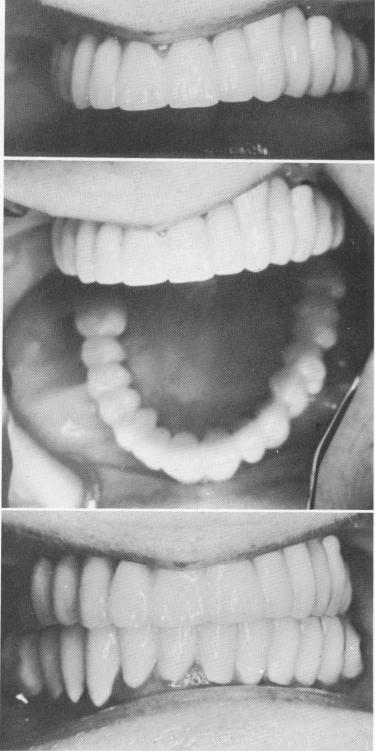

Fig. 11-133. The biscuit-baked prosthesis was tried. All necessary occlusal and esthetic changes were done during the final glazing process of the porcelain.

Fig. 11-134. The final prosthesis cemented in place.

1 Biscuit baked maxillary prosthesis tried.Occlusal,esthetic changes done

2 Final maxillary prosthesis cemented in place